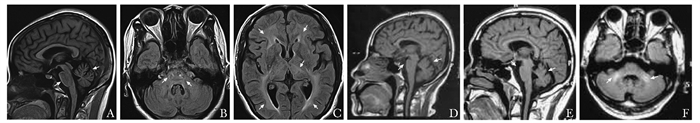

成年肾上腺脑白质营养不良患者临床及遗传分析

王梦文, 伍楚君, 张在强

2022, 1(2): 130-136. DOI: 10.12376/j.issn.2097-0501.2022.02.006

摘要 HTML全文 PDF